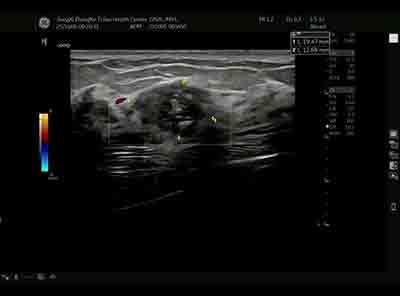

血流模式的精细评估 乳腺良恶性肿瘤的血流特征存在显著差异。E11采用的超微细血流成像技术具有突破性意义:

准确区分肿瘤边缘与内部血流分布 恶性肿块通常表现为血流丰富、走行紊乱、动静脉瘘形成,而良性病变血流相对稀疏、走行规则。这种差异为鉴别诊断提供了重要参考。